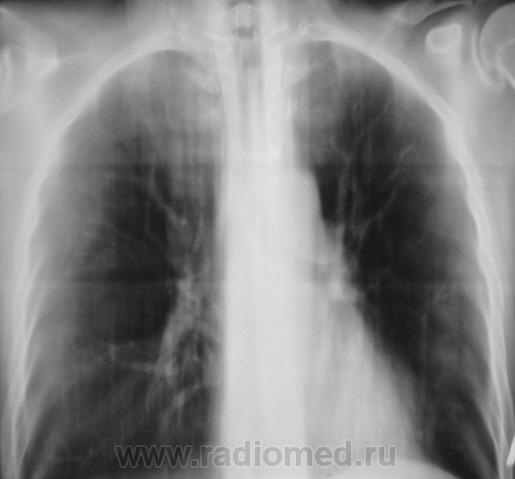

После курса лечения.

После лечения динамика очень хорошая.